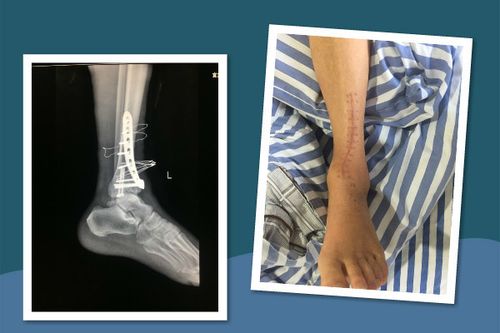

脚踝骨折照片高清图片,脚踝骨折打石膏图片

脚踝骨折及恢复过程记录

3米高处坠落致脚踝粉碎性骨折,仅15天即可下地行走

脚踝骨折打石膏图片

外踝骨折图片

脚踝骨折ct图片清晰